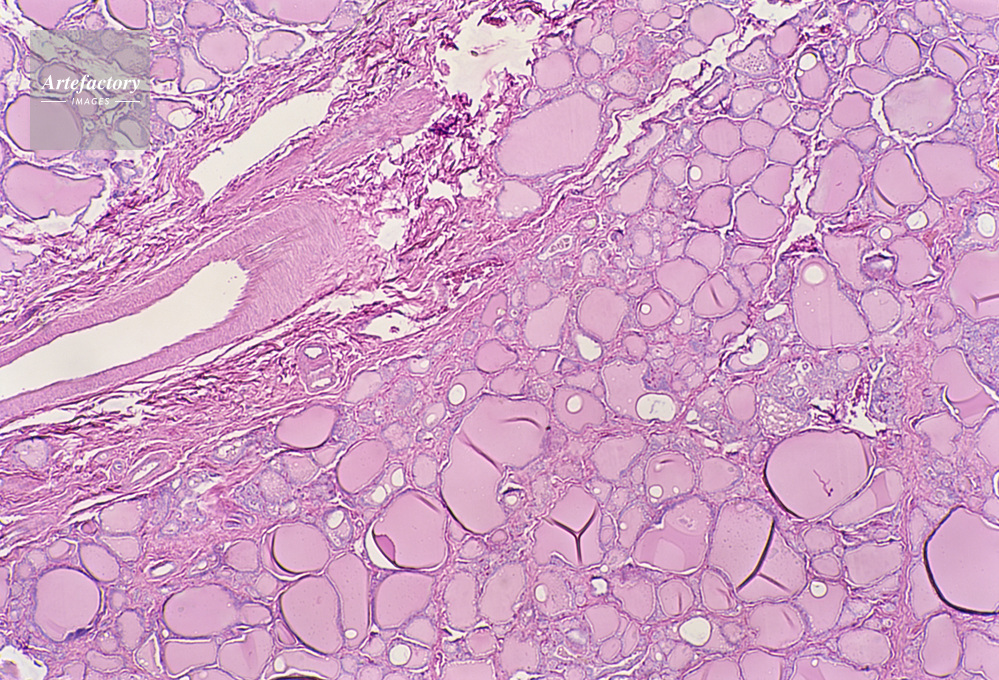

| キャプション | 甲状腺,人間,20倍 | 制限事項 | ||